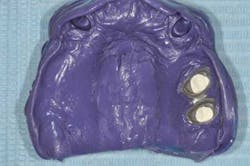

Figs. 5a and b: Impression for the RPD framework including the PFM frameworks and mounting

- Impressions and fabrication of the RPD and implant abutment metal frameworks.